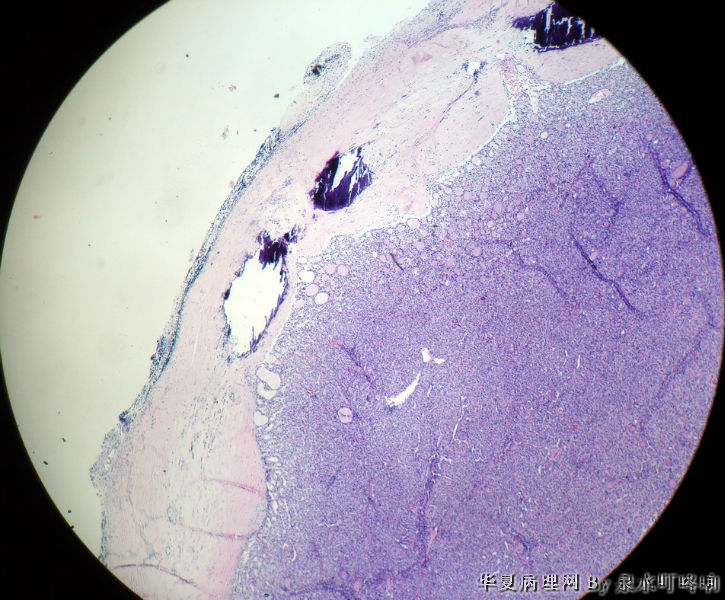

120212,女,55岁,左颈部肿物七年余。

大体:灰白肿物一个,大小约2.1×1.5×1.3厘米。表面光滑,包膜完整,切面灰白,部分包膜有钙化。

与手术医生沟通,肿物位于左颈部靠近甲状腺部位,比较浅(门诊手术),手术医生认为是淋巴结部位。

厚包膜、蕈状浸润----滤泡癌。